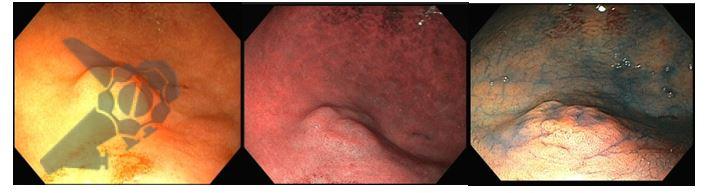

Endoscopia Digestiva Alta revela lesão plano-elevada (0-IIa de Paris), com superfície vilosa, aspecto regular, com bordas mal delimitadas, localizada na grande curvatura do antro proximal de 12 mm (Fig.1)

Biópsias: adenoma com displasia de baixo grau.